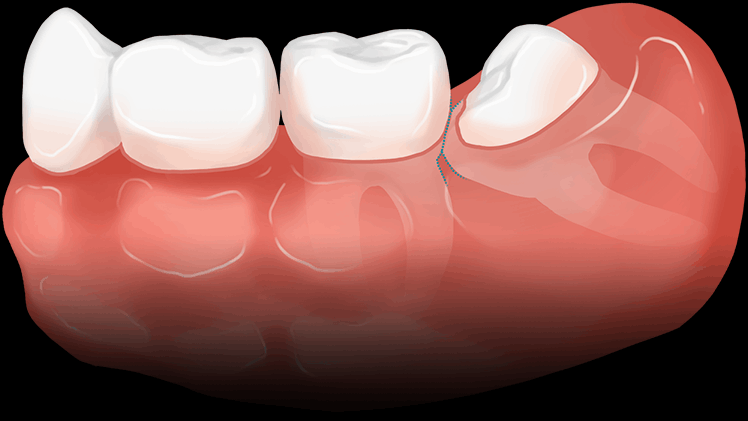

사랑니가 반듯하게 나서 씹는 기능을 할 수 있다면 굳이 뽑지 않아도 됩니다.

하지만 잇몸에 매복된 채 자라나는 사랑니는 구강관리가 어려워 인접 치아에 충치와 염증을 쉽게 불러일으킬 수 있습니다.

사랑니가 잇몸에 덮여있어 일부만 보이는 경우 치아와 잇몸사이에 세균이 서식하여 충치 및 염증을 일으킬 가능성이 높습니다.